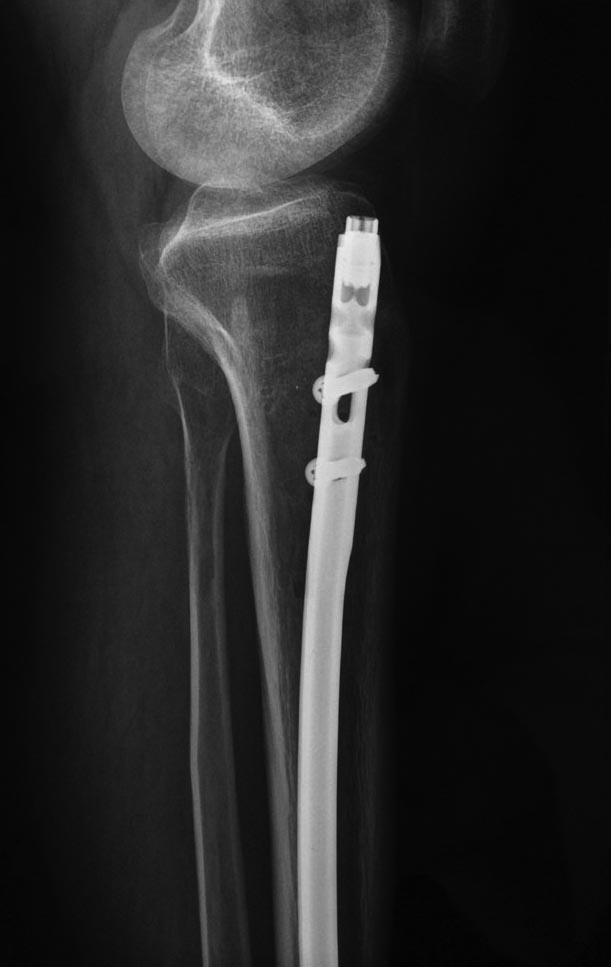

В феврале 2014 г выполнил первым этапом: Фиксацию ложного

сустава в АНФ с восстановлением осей сегментов. Через семь дней БИОС с

рассверливанием.

После операции - вальгус голеностопного сустава. Гладкое течение

послеоперационного периода. Нагрузка по переносимости боли. Через 6

недель динамизация, через 2 недели стали мигрировать 2 фронтальных

винта. Пытался подкрутить, пришлось удалить.